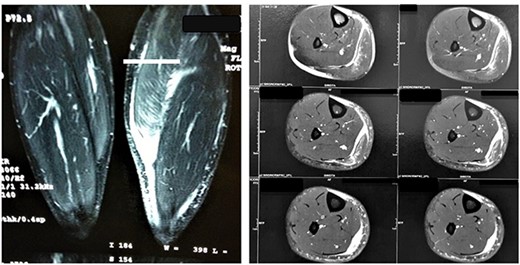

Both patients denied steroids use. They were evaluated by radiographs and MRI and classified by O’Donoghue classification system as a grade III injury in both cases. Lesions were found at the medial head of the gastrocnemius muscle myotendinous transition. In Case 1, 5 cm retraction was measured and in Case 2, 7 cm. Figure 2 shows imaging findings.

MRI images of Patient 1 and Patient 2, respectively. In the left image, a coronal section of the two legs weighted in a sensitive liquid sequence shows edema accompanied by a distal gap in the lesion topography. In the right image, we see multiple axial slices also showing fluid accumulation and muscle retraction in the musculotendinous transition.